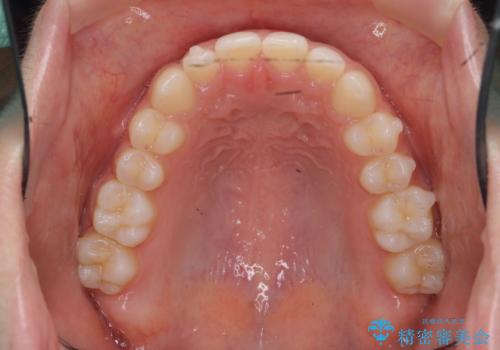

前歯のガタつき・ねじれを治すマウスピース矯正

マウスピース矯正を始める前にワイヤー部分矯正を行ったことで改善のしにくい歯のねじれをしっかりと治すことができました。

- 治療期間

- 1年